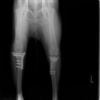

左後肢の挙上を主訴に来院されました。触診にて両関節の前方引き出し兆候、両膝蓋骨の内方脱臼を認めました。関節液検査より免疫介在性多発性関節炎は否定的でした。レントゲン検査にてfat pad signを伴う関節炎が認められたことから、前十字靭帯断裂と膝蓋骨内方脱臼(左GradeⅢ 右GradeⅢ〜IV)併発と診断し、手術を行いました。

手術は片足ずつ行い、両膝とも術中の関節鏡検査にて前十字靭帯の完全断裂と半月板損傷を確認しました。TPLO、半月板切除と滑車溝形成を始めとした膝蓋骨脱臼整復術を実施いたしました。膝蓋骨の安定化を測るために外側支帯を強固に縫合し、内側支帯は切除し縫合せずに開放状態にしています。

術後左後肢正面像

術前のTPAは左後肢33.1°右後肢26.8°でしたがTPLO実施により左後肢5.5°右後肢12°に矯正されました。